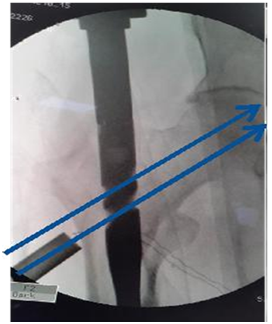

Proximal reaming must to accommodate broad proximal part of nail

1. Reamer to be pushed medially at entry point to break cortex so that reamer and nail is not displacing the fracture, as it leads to malposition of screws in head (Figure 18).

2. Reaming on guide wire up to the length and breadth of proximal part of nail up to lesser trochanter. Otherwise nail may not progress distally (Figure 19).

3. Reaming parallel to outer cortex/intact anterior or posterior cortex.

Figure 18 Cut a correct path. Reamer to hit lateral edge of proximal fragment for correct path.5

Figure 19 Proximal reaming must to accommodate broad proximal part of nail.